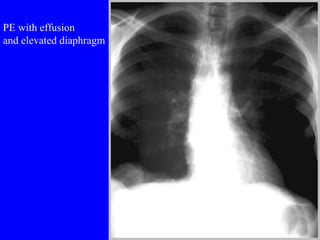

Pulmonary embolism (PE) is a common and potentially fatal condition where blood clots block arteries in the lungs. An estimated 5 million venous thromboses occur annually worldwide, with 10-30% of cases resulting in PE. Risk factors include immobilization, surgery, cancer, and estrogen use. Diagnosis involves assessing clinical probability based on symptoms and risk factors, followed by tests like D-dimer, chest imaging, ultrasound, V/Q scan, CT, or angiogram. Treatment aims to prevent further clotting with anticoagulants like heparin and warfarin, provide supportive care, and in some severe cases utilize thrombolysis or embolectomy.